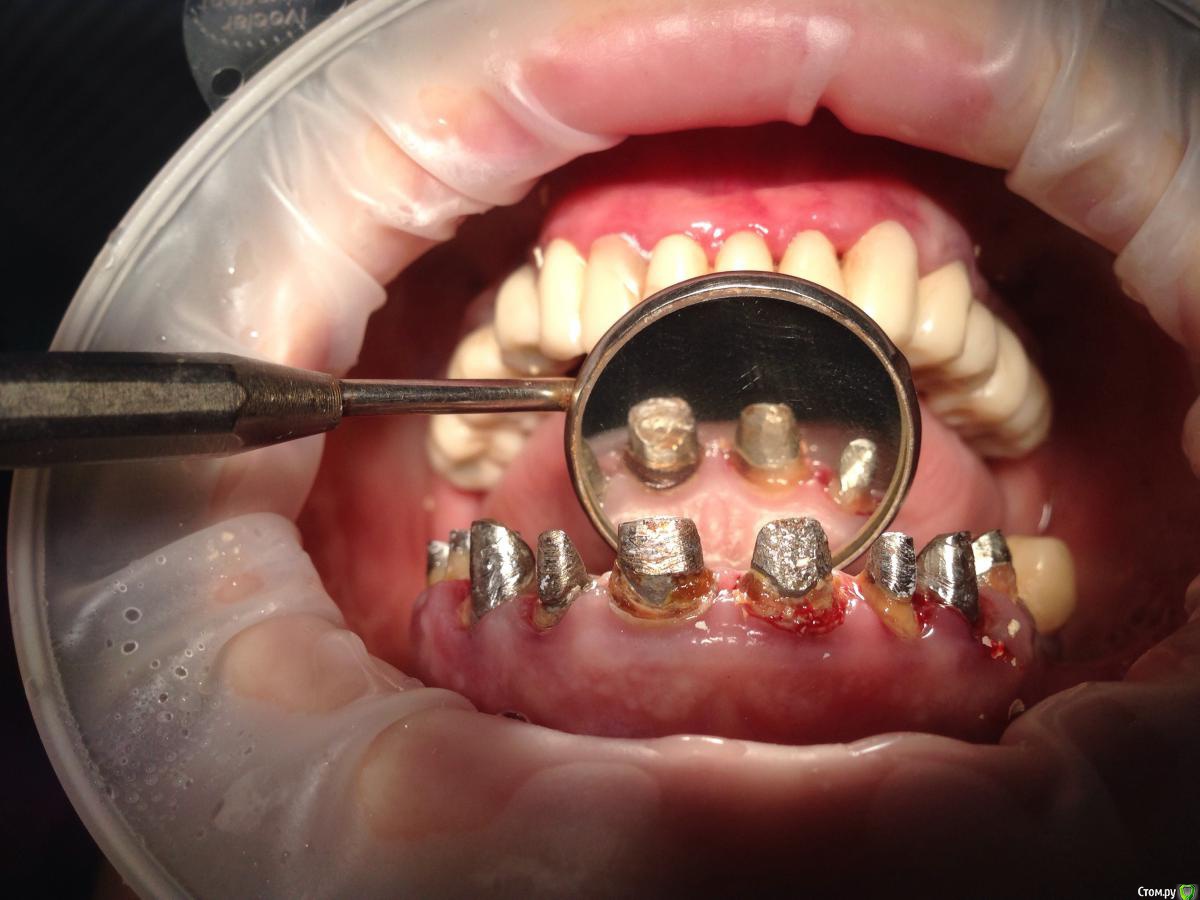

Bratok Опубликовано 17 июля, 2016 Поделиться Опубликовано 17 июля, 2016 Коллеги, всем привет! Вот такая пациентка в клинике был доктор у нас с 20 летним стажем, она уехала сейчас и не работает. Протезировала пациентку.. Были изготовлены временные коронки.. Судя по всему страдал герметизм и под ними все печально.. Десне и феррулу хана...Чтобы Вы тут посоветовали? Планировалось к нее мк... Сделать в 3 сегмента 3-3 и остальные блоком. Какой прогноз? Лет 5? Извиняюсь за качество rg.. Ссылка на комментарий

Bratok Опубликовано 16 августа, 2016 Автор Поделиться Опубликовано 16 августа, 2016 Говорил с пациенткой о ее состоянии, пока что не хочет ничего удалять. На свой страх и риск просит протезировать то что есть.. Пока я в отпуске, сделал ей новые времянки чуть герметичее..на мой взгляд если вдруг она снова пропадет..я ей предложил делать маленькими мостами и если будут вылетать то готовиться к all on 6 на верху..ну или другие варианты.Ну и нижние на имплантатах протезируем Ссылка на комментарий

Kolchanov Опубликовано 16 августа, 2016 Поделиться Опубликовано 16 августа, 2016 Ну а почему бы не вытащить, там где надо вытащить, при необходимости удлинить тем или иным способом и т.д.? На кариозную эту фигню будете протезировать? 1 Ссылка на комментарий

korotkevich Опубликовано 17 августа, 2019 Поделиться Опубликовано 17 августа, 2019 (изменено) Коллеги, всем привет! Вот такая пациентка в клинике был доктор у нас с 20 летним стажем, она уехала сейчас и не работает. Протезировала пациентку.. Были изготовлены временные коронки.. Судя по всему страдал герметизм и под ними все печально..Десне и феррулу хана...Чтобы Вы тут посоветовали?Планировалось к нее мк...Сделать в 3 сегмента 3-3 и остальные блоком. Какой прогноз? Лет 5?Извиняюсь за качество rg..В идеале доставать вкладки, убирать кариозные ткани, делать билдапы и затем либо хирургическое удлинение, либо вертипреп, либо и то, и другое; и металлокерамические коронки с гирляндой, таким образом сохраните максимально то, что есть Изменено 17 августа, 2019 пользователем korotkevich Ссылка на комментарий